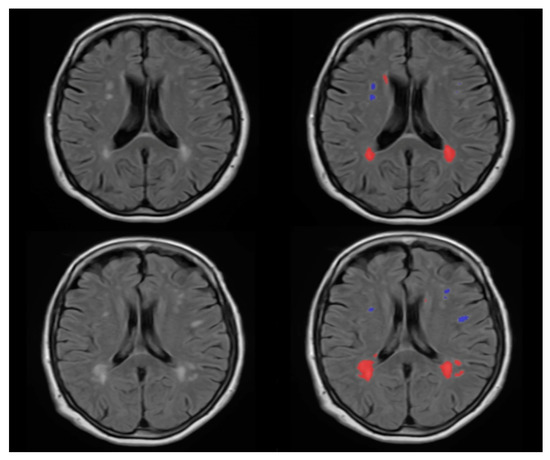

2.4. WMH Segmentation